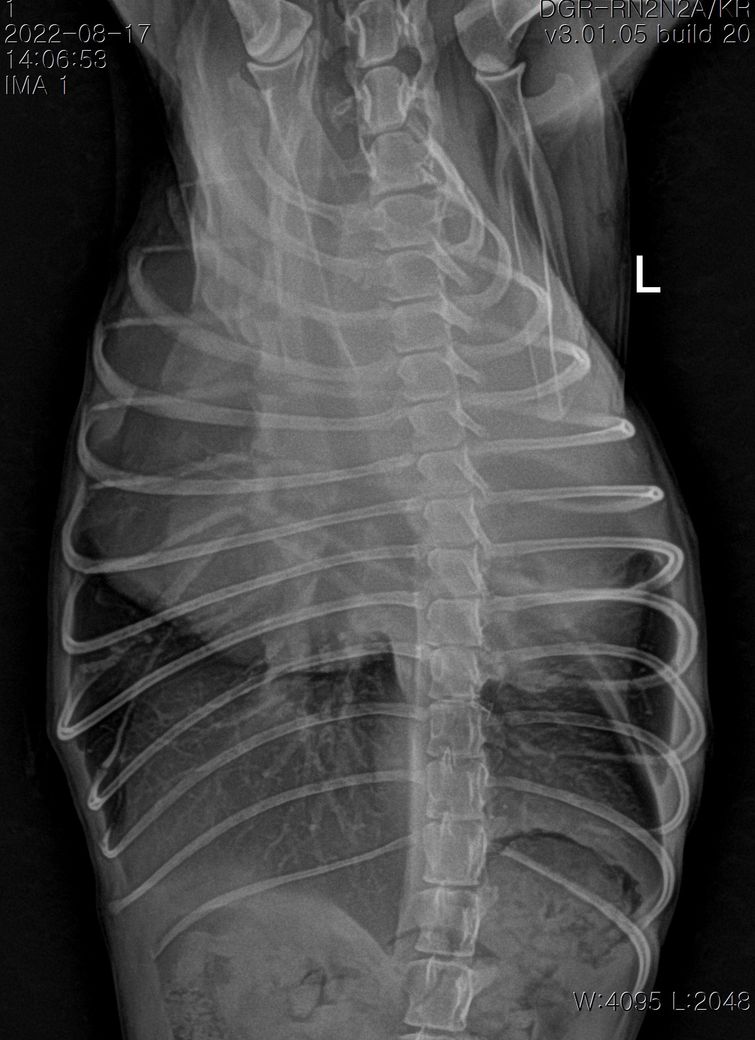

강아지 폐종양 의심되는데 봐주실 수있을까요?

11살강아지 입니다.

폐에 종양의심소견이 보인다고 해서요.

7월부터 기침을 간헐적으로 하다가 최근 심해져서 병원에 갔는데 엑스레이 상 폐종양이 의심된다고 해서요.

첨부해주신 사진만을 기초로 볼때 폐종양인 경우 좌측 폐전엽부의 종양이, 폐종양이 아닌 경우 종격동내의 종양 특히 흉선종양의 가능성이 높아 보입니다.